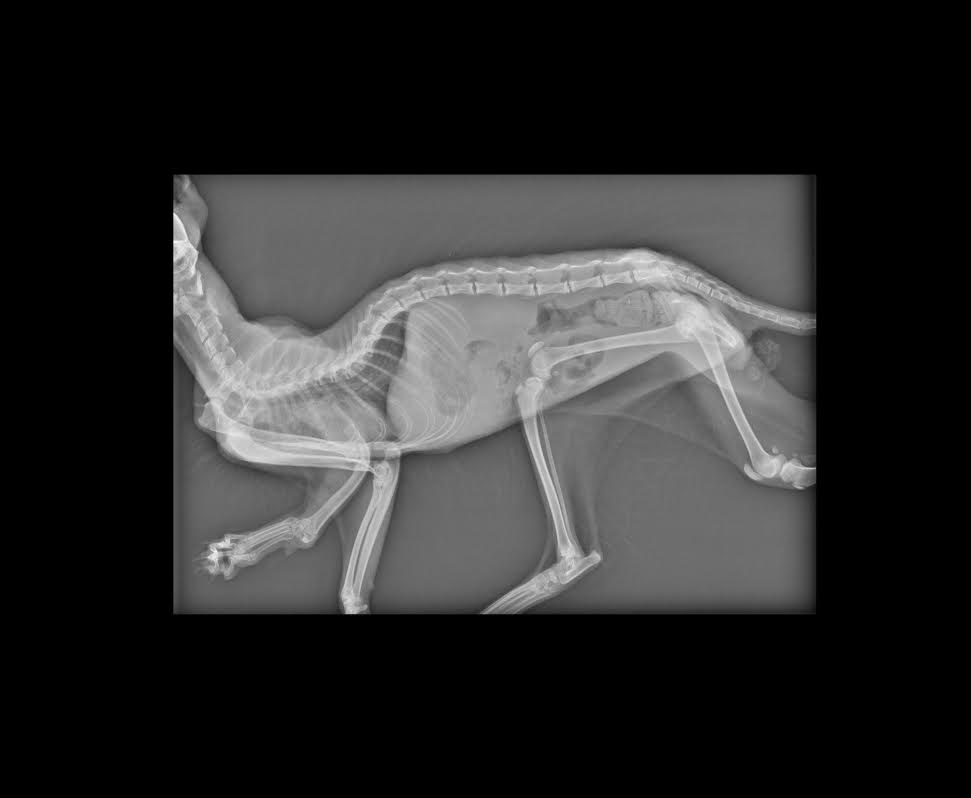

毛髮雜亂,有輕癱.血尿.虛弱.前肢脘關節脫臼.右側腸薦關節脫位 .右側髖關節脫位,

其實醫生說了那摸多很艱深的疾病,

在X光下說明了一切...

因為四肢有三肢都缺少一塊骨頭...

這不是後天造成是先生的...

4.X-ray 400*3